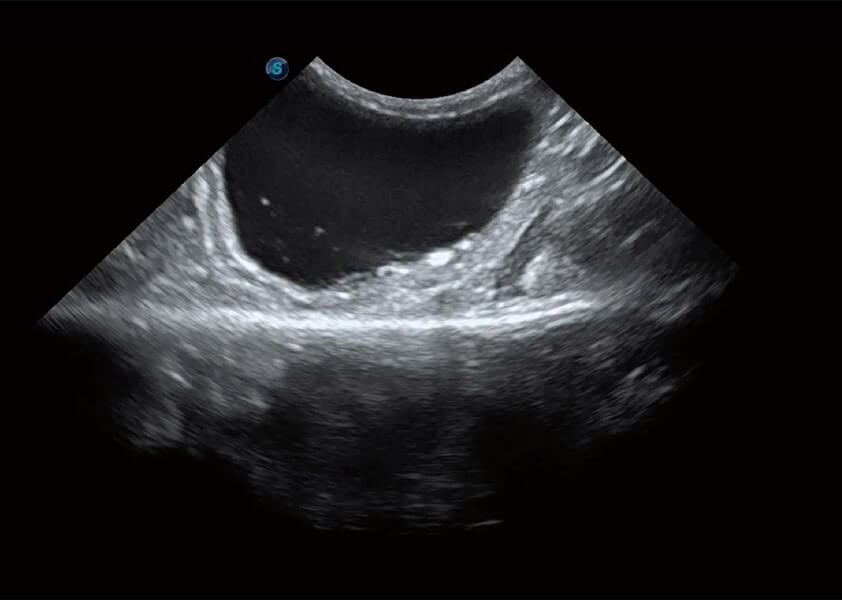

ProPet 60 作为一款高端台式动物超声设备,为动物医生的日常诊断提供了一系列贴合动物临床需求、解决临床实际问题的高级成像功能。凭借全系列高清探头,满足医生对腹部、心脏、生殖、浅表、肌骨等成像的所有需求,切实帮助您提升检查效率,提高诊断信心。

动物是人类最亲密的朋友和最值得信赖的伙伴。milan米兰也一直致力于探索动物专用的超声影像解决方案。 全新推出的ProPet系列,是milan米兰在动物超声影像智能化、专业化、精准化的一次跨越式革新。动物不能用言语来表述自己的不适,通过超声影像,ProPet系列搭建了动物医生与不同物种沟通的“桥梁”,为动物医生注入了“治愈之力”。